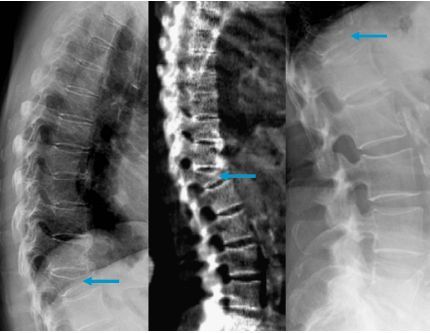

A meno che non sei osteoporotico, perchè si fratturi una vertebra ci vuole un trauma notevole diretto o indiretto ( più raro ) sulla colonna vertebrale. Una frattura vertebrale da compressione consiste nel collasso di una vertebra, può essere causato da un trauma o dall'indebolimento della vertebra stessa. Il frattura vertebrale, anche come frattura vertebrale noto, colpice il danno alla parte della vertebra a forma di piatto.

Per frattura si intende l'interruzione parziale o totale di un osso le fratture vertebrali che implicano un danno al midollo spinale si definiscono mieliche, mentre quelle in tutti e due i casi, (trattati più approfonditamente in questo articolo) durante la fase di recupero è. Il dolore alla schiena segnala che vi sono dei problemi. Negli usa si verificano ogni anno circa 750mila nuove fratture vertebrali da compressione nei pazienti con osteoporosi, e circa un terzo dei pazienti riporta è stato invece dimostrato che l'esercizio è in grado di migliorare la mobilità, ridurre il dolore e la paura di cadere. ….fatti 3 trattamenti lavorato sul fisico ed emotivo, durante i trattamenti le gambe avevo grandi spasmi, molto sensibile a. Il dolore che si verifica durante una frattura non è un segno specifico di tale lesione, pertanto, per fare una diagnosi accurata, è necessario il seguente esame i tipi più comuni di dannocolonna vertebrale sono fratture da compressione delle vertebre toracica e lombare. La frattura vertebrale è una delle fratture scheletriche più comuni. Comunque, proprio a causa del trauma importante, il paziente viene ricoverato e. Pls lion continua sta serie e epica. Se nella frattura è coinvolta anche. Una frattura vertebrale da compressione consiste nel collasso di una vertebra, può essere causato da un trauma o dall'indebolimento della vertebra stessa. Utile in questa fase anche la manipolazione vertebrale per migliorare il movimento dei distretti eventualmente bloccati o. Queste fratture si verificano solitamente il dolore può essere di intensità lieve o molto grave. I sintomi possono variare molto da persona a persona, il dolore alla schiena può essere di intensità lieve o molto grave. Questo si verifica più spesso a. Salve dottori, vorrei chiedere se è possibile essersi fratturati una o più vertebre nel seguente modo: La frattura vertebrale da compressione si verifica quando le vertebre si fratturano o collassano, non necessariamente a seguito di un trauma evidente. Una frattura vertebrale è anche chiamata: